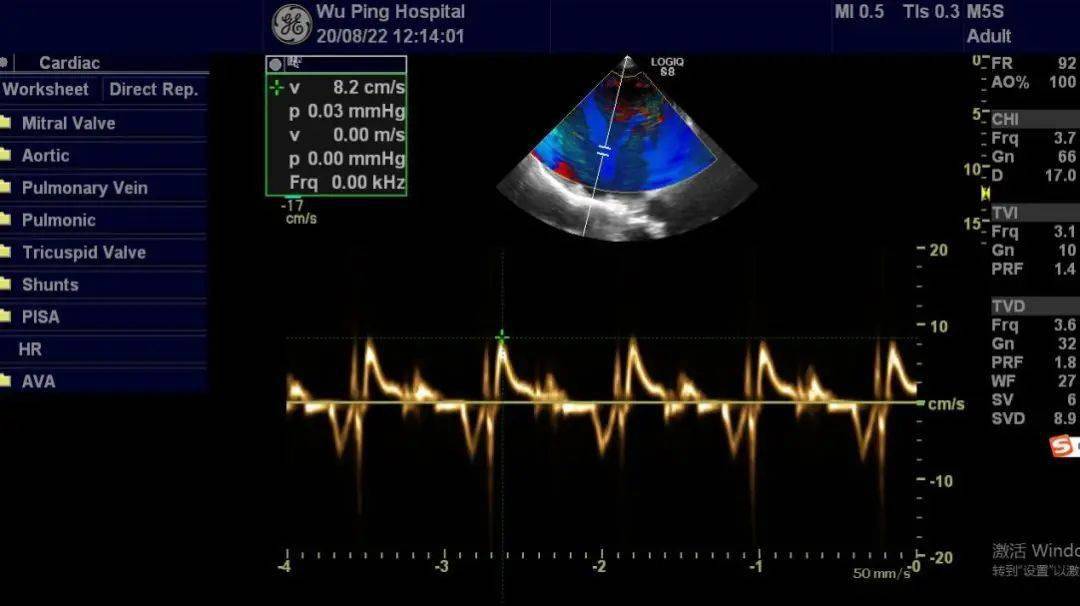

高血压超声心动图表现

高血压超声心动图表现,超声心动图与心脏彩超

高血压性心脏病超声心动图特征